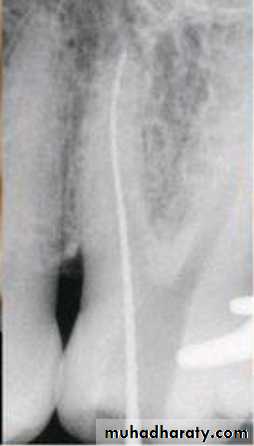

Standardized tech. Illustration